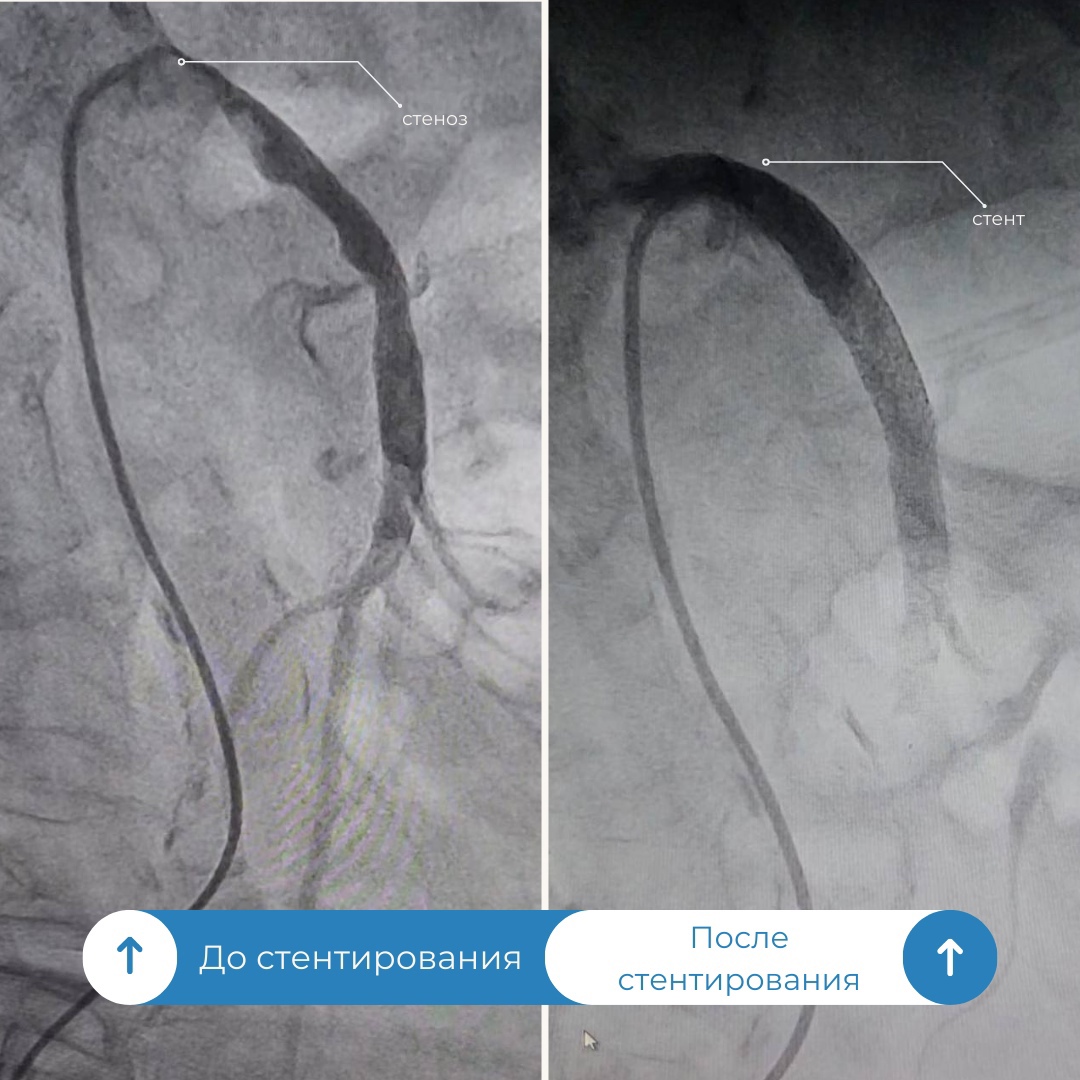

Врачи окружной Нижневартовской больницы успешно провели операцию у женщины с заболеванием, которое встречается у 2-4% пациентов. В приемный покой медучреждения поступила пациентка с жалобами на высокое давление и боли в животе и за грудиной. После проведения компьютерной томографии специалисты обнаружили сужение верхней брыжеечной артерии, которая снабжает кровью кишечник. Этот диагноз характеризуется высокой смертностью, которая колеблется в пределах 70-90%.

«Усугублялась ситуация и тем, что у пациентки наблюдался выраженный кальциноз, когда соли кальция откладываются на стенках сосудов. Поэтому было решено оценить варианты и возможности развития событий в рентген операционной. Через прокол в бедренной артерии в аорту мы ввели диагностический катетер и установили его в устье верхней брыжеечной артерии, затем ввели контрастное вещество и под рентген-контролем выявили критический стеноз» , – прокомментировал операцию врач по рентгенэндоваскулярному лечению Уйгунжон Жахонгиров.